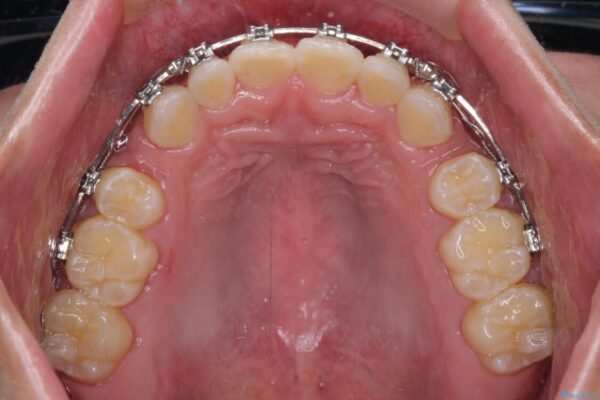

治療途中

• 口元の突出感を改善 受け口傾向の咬み合わせの抜歯矯正 治療途中画像